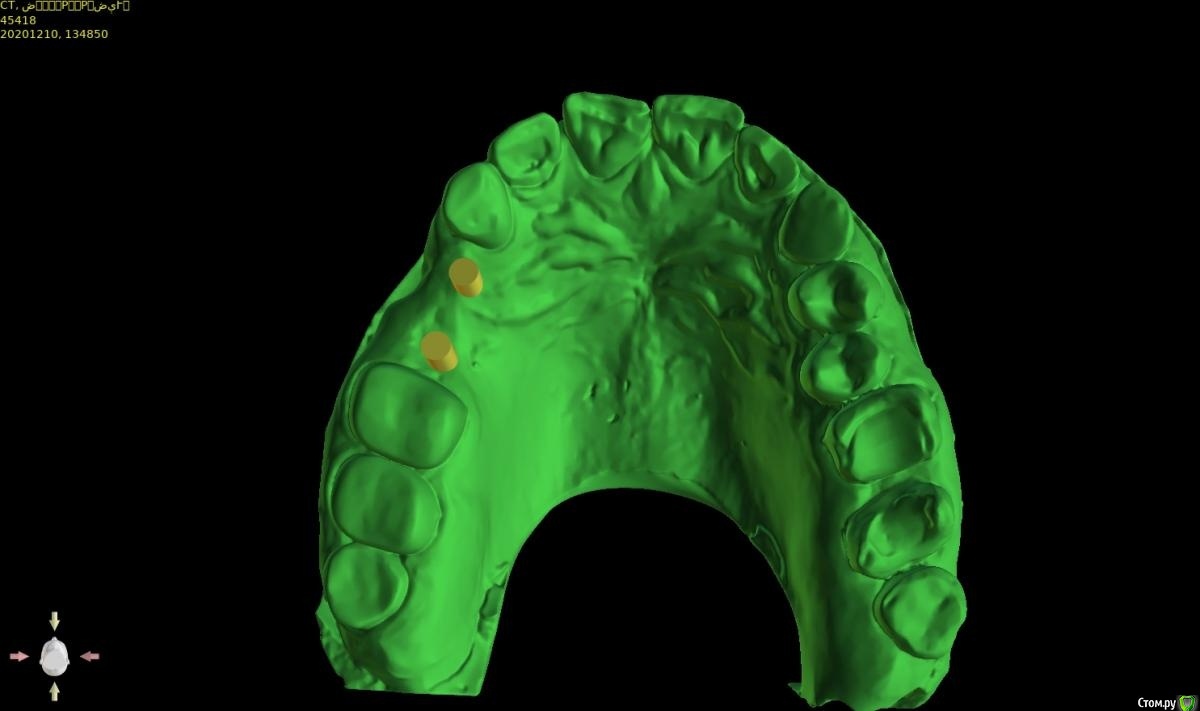

Женька Опубликовано 14 февраля, 2021 Автор Поделиться Опубликовано 14 февраля, 2021 (изменено) @Irouil, не слишком ли нёбно? как считаете? И в случае такого позиционирования, стоит ли перекрывать эту вестибулярную ямку сст? (подставил зубы виртуальные и понял, что там сосочек надо формировать будет, потому нужно объём тканей создавать) Делаем шаблон под пилот И всё-таки хотелось бы от ортопедов услышать ответ, пожалуйста: Я правильно думаю, что правильное ортопедическое положение может быть и с вестибулярным наклоном, главное чтобы шахта не в сторону губы верхней смотрела?) (утрирую) Изменено 14 февраля, 2021 пользователем Женька Ссылка на комментарий

Fin Опубликовано 14 февраля, 2021 Поделиться Опубликовано 14 февраля, 2021 1.5 как то очень близко к зубу Ссылка на комментарий

Женька Опубликовано 14 февраля, 2021 Автор Поделиться Опубликовано 14 февраля, 2021 Ну, 1.5мм там есть... но согласен, кажется прям впритык Ссылка на комментарий